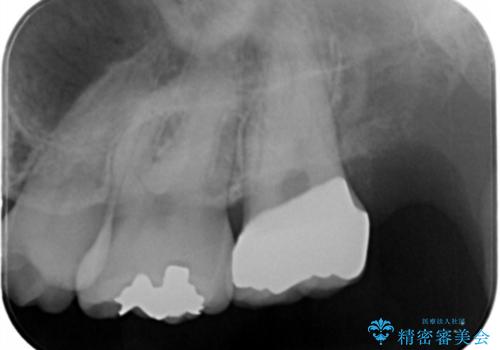

白い被せ物が入りとても満足して頂けました。

セラミックの被せ物は銀歯に比べて虫歯の再発のリスクが低いです。